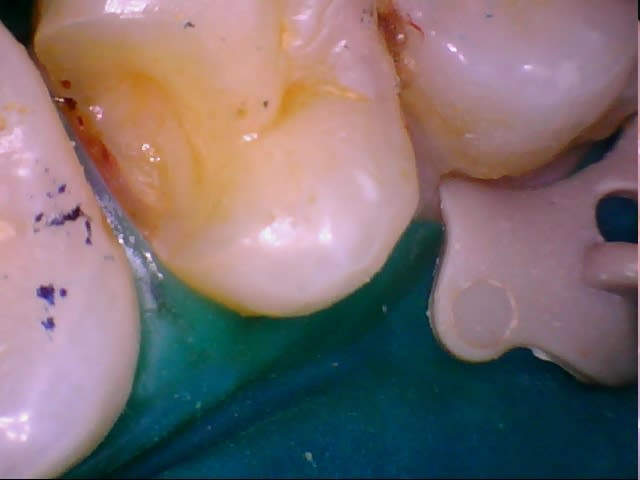

Dscn0753 ahgw2u - Eugenol

Dscn0750 x2wbw9 - Eugenol

Il aurait fallu une photo en vue occlusale. D'après ce que je vois, un joli composite direct doit être largement suffisant. Les prémolaires du bas sont des dents qui se cassent rarement, surtout s'il n'y a qu'une cavité proximale et non MOD (en plus, largement supragingivale)

Il n'y a pas qq chose de louche au mésial de la 47 ?

et comme ceramik, il y a un truc louche sur 47

Refaire aussi la 47 (reprise de carie) et la 46 qui sont dégueulasses.

Pour la 45, un truc sans tenon (soir un compo direct avant de prendre l'empreinte pour 46, soit un inlay).